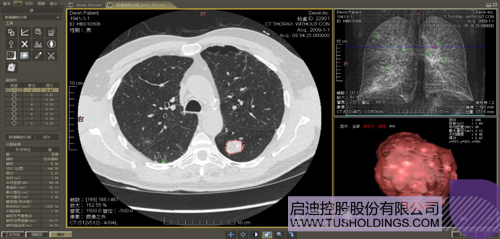

數字肺產品肺癌計算機輔助診斷

醫療影像智能診斷技術醫療影像智能分析是指運用人工智能技術、計算機視覺技術以及計算幾何技術對醫療影像進行自動分析,幫助醫生定位病癥、分析、跟蹤病情,并通過量化數據輔助醫生做出診斷,目前其旗艦產品“數字肺”已經覆蓋多種肺部疾病的早期檢測、診斷、跟蹤、術前規劃等完整的醫療流程。在臨床實踐中,超過80%的醫療數據來自醫療影像,這些影像數據通常需要專業醫生進行解讀,工作的重復性高、效率偏低。如果能夠運用智能影像分析技術,同時結合臨床表現以及既往病例進行全面分析,那么就可以大幅度提升影像診斷效率和準確性,讓專業醫生的寶貴時間集中在復雜病情的診斷和治療等環節。

數字肺——肺結節手術規劃系統